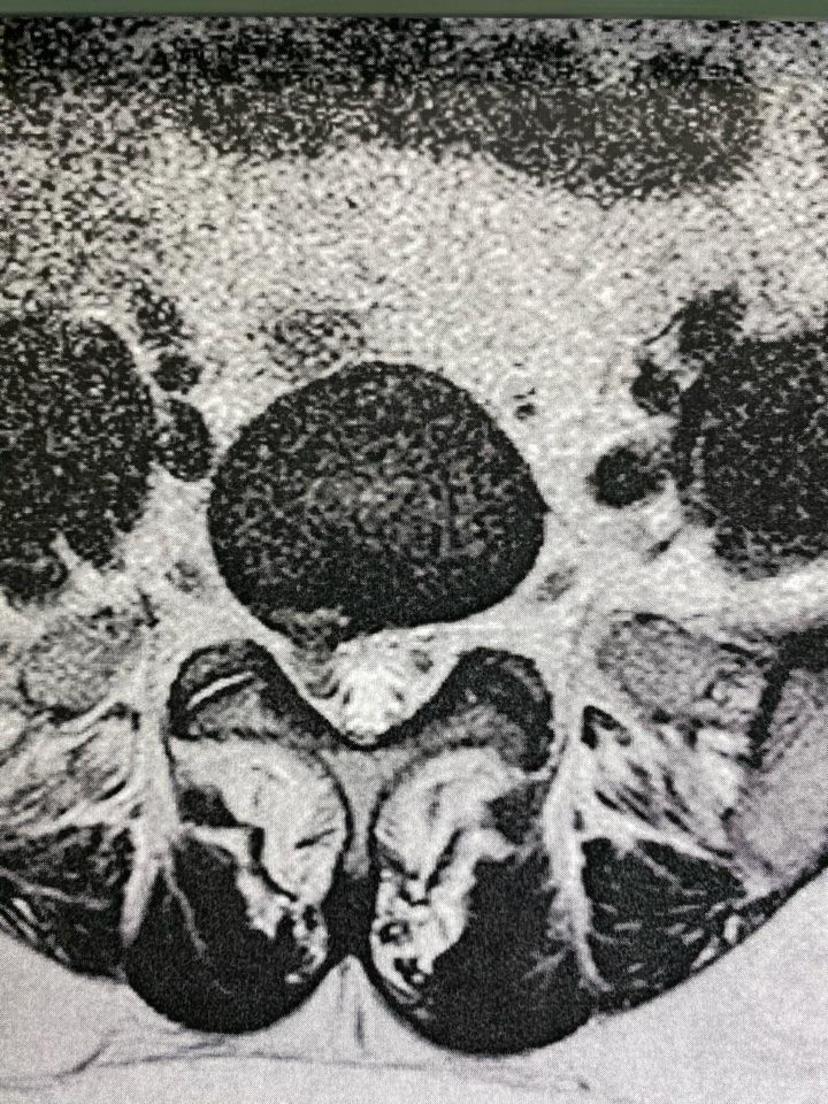

公司职员腰5-骶1椎间盘突出,右下肢疼痛麻木走不了路,利用假期三天时间(住院-手术-出院),完全恢复正常!